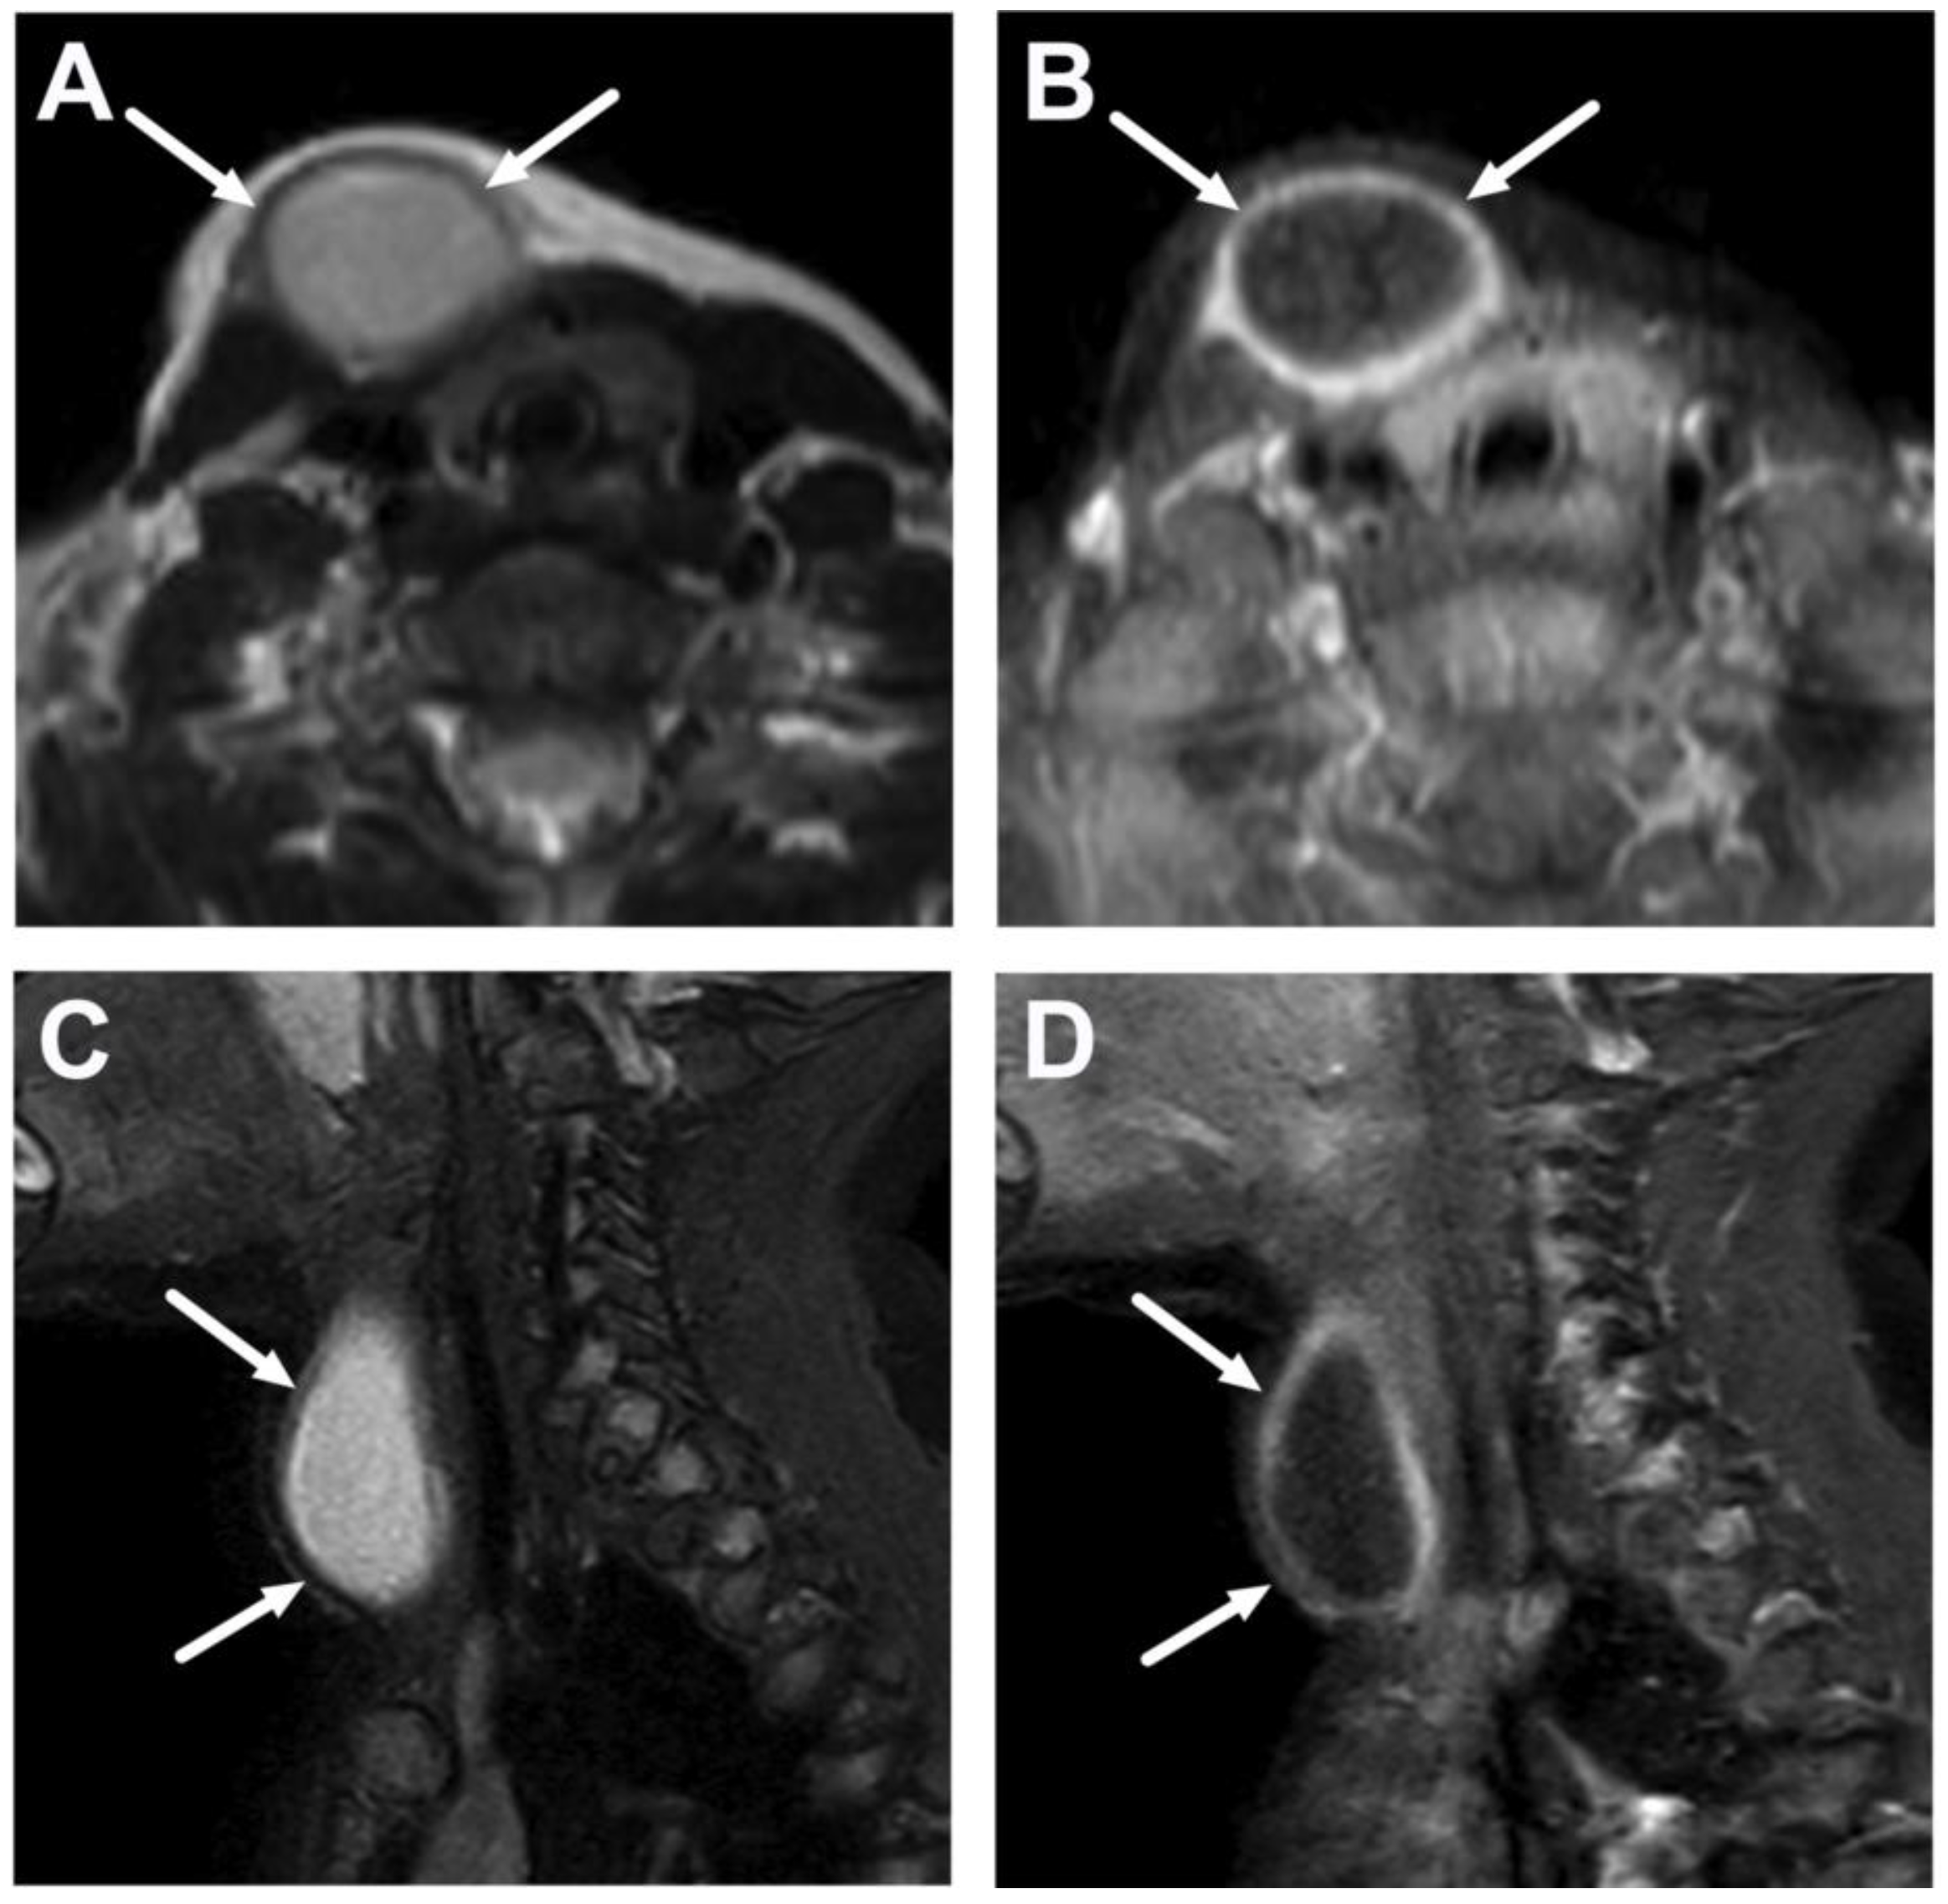

5.2. Cystic Masses

| Cystic masses and potential neoplasms | Whole protocol | Identification of cystic component vs. neoplastic tissue, both with or without signs of infection. | Relevant differential diagnostics; exclusion of findings requiring immediate interventions. | Differential diagnosis may be limited and needs clinical correlation; biopsy may be required. |